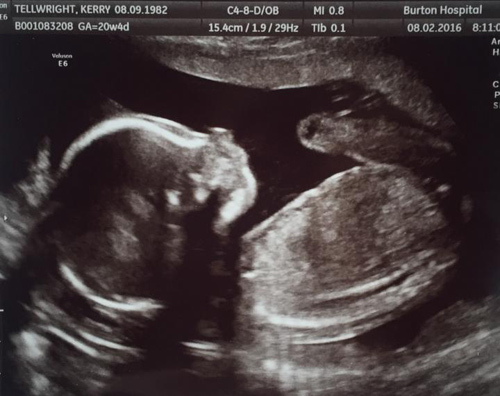

Kerry Tellwright và vị hôn phu Craig Hill đã vô cùng vui mừng khi họ phát hiện có bầu sau 8 năm cố gắng có con. Trong thời gian đó, họ đã phải đối mặt với nỗi đau khổ với một lần sảy thai cặp sogn sinh và 2 lần thụ tinh ống nghiệm không thành.

Bà mẹ này có thai kỳ khá khỏe mạnh.

Chỉ vài ngày sau đó, vài ngày 17/6 năm ngoái, bà mẹ 34 tuổi được đưa đến bệnh viện và tại đây các bác sĩ đã phát hiện ra Kerry mắc chứng bệnh cực hiếm dẫn tới vỡ gan và lá lách và đau khổ hơn cả là bé trai trong bụng cô đã qua đời ở tuần 39 thai kỳ.